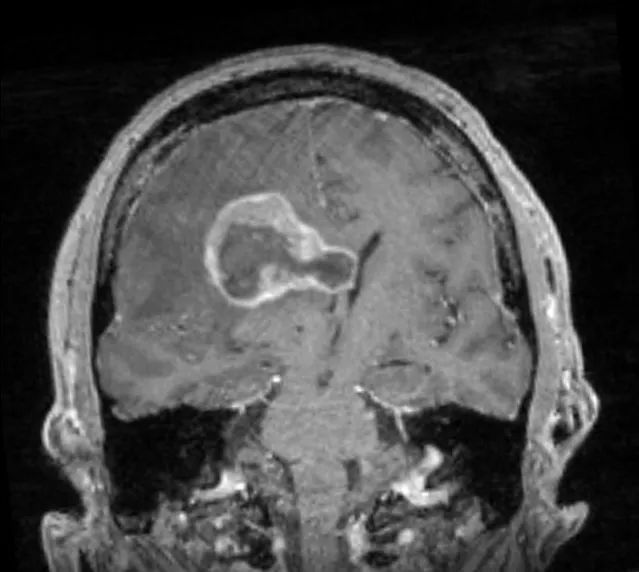

患者为55岁男性,因“跌倒频率增加和左侧肢体无力1周余”就诊。 3年前患者曾于外院行肺癌切除术,但患者后来失访,且无法明确癌变性质和分期。 入院时神经系统查体无异常。 外院头颅CT见颅内出血灶,胸腹盆腔CT未见异常。 立体定向颅内病变活检提示肿瘤为低分化转移癌,细胞标志物检测考虑鳞状细胞癌。

立体定向导航下行右额开颅。 鉴于肿瘤位置深,计划在60mm长BrainPath(厂家NICO)管型牵开器辅助下以微侵袭方式切除该肿瘤。 术前借助导航系统于右侧额叶寻找对应肿瘤长轴的脑沟并以此为进入点确定术中路径,手术通道与肿瘤长轴平行可以有效降低纤维传导束和基底节的损伤风险。

右额开颅最重要的注意事项就是骨瓣应该位于冠状缝前方以防误伤中央前回。 如果患者为左利手,应避开额下回,尤其三角部和盖部,以免损伤Broca区。 肿瘤尾端侵犯尾状核、内囊前肢和侧脑室额角,部分肿瘤已经毗邻室间孔,因此可能与穹窿、丘纹静脉和尾状核静脉关系密切。

术后患者安返神经ICU。 术后使用地塞米松并于1周内迅速减量撤药。 使用左乙拉西坦500mg bid预防性抗癫痫。 术后第1天复查MRI见肿瘤近全切。